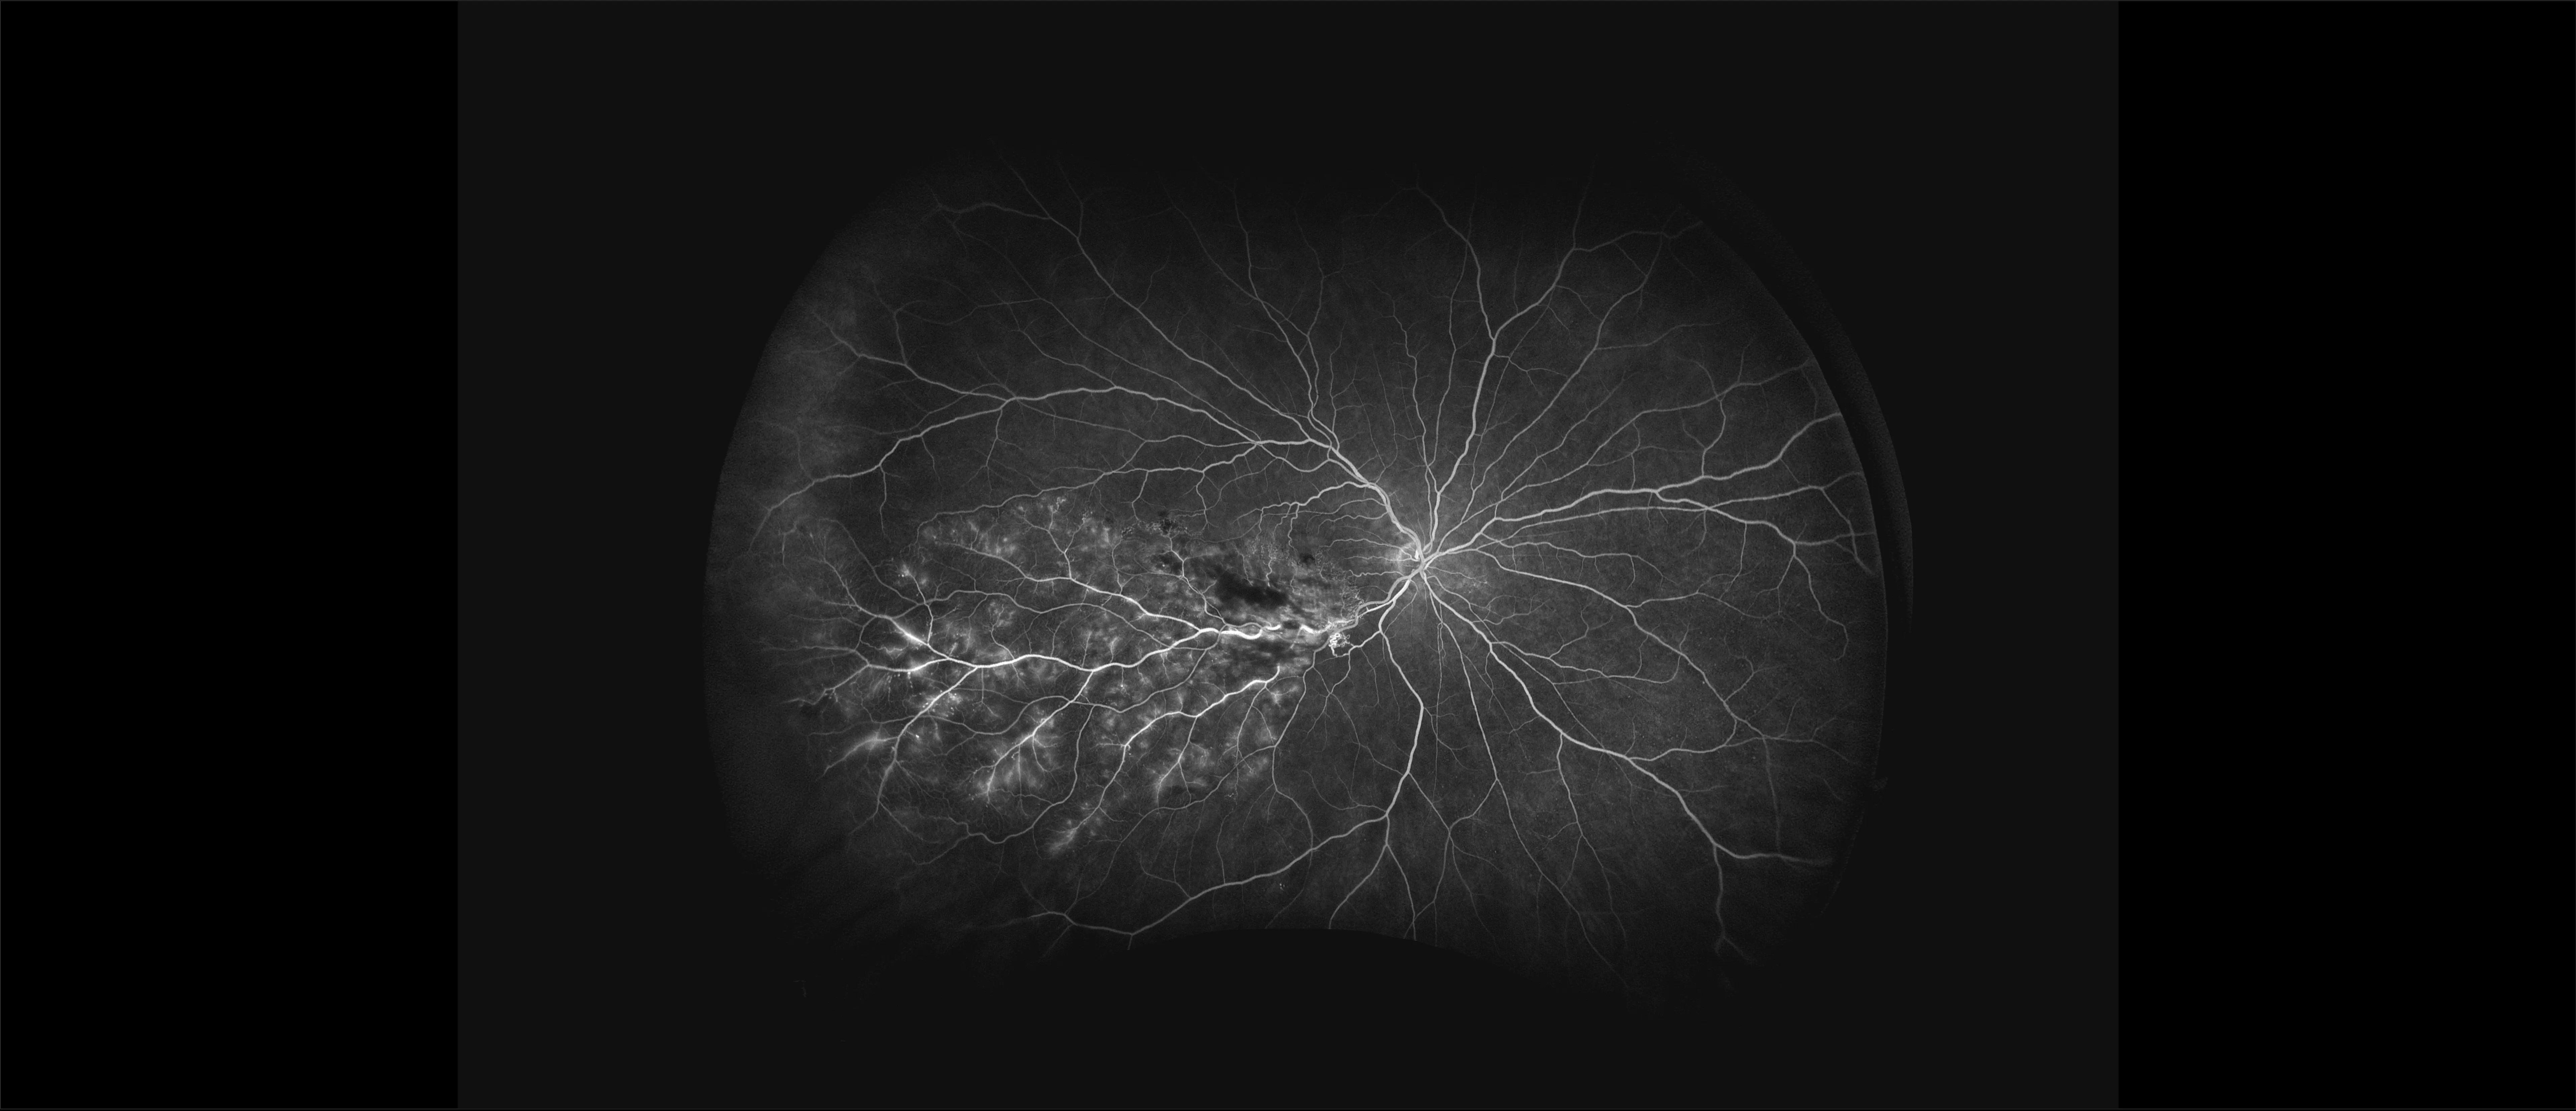

optomap® Recognizing Pathology

This material is designed as a searchable reference resource to support clinical decision-making. The information contained here should be used as general guidance when viewing optomap and OCT images from Optos devices. The differential diagnosis should be made under the direction of the responsible physician. These images were taken on the latest ultra-widefield optomap devices.

The Cases and Images

optomap Recognizing Pathology is searchable by pathology and/or optomap image modality. You may search by multiples of each selection. Each individual case is represented by the accompanying thumbnail image. Most cases include several different optomap image modalities. To view a full description of the case, please click on the thumbnail. Each image in the case will be made available through our OptosAdvance software which provides multi-dimensional visualization of digital images to aid in the analysis of anatomy and pathology. Support and pathology definitions can be found by selecting one of the buttons, above. Should you have questions, please complete the form below.